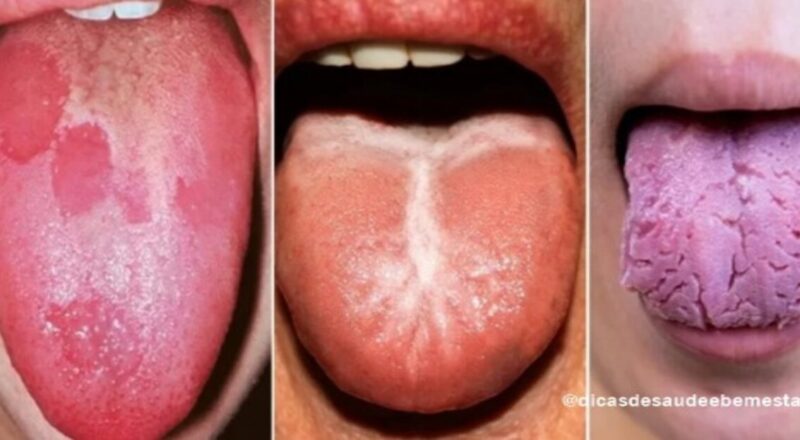

Continue lendoFique atento aos sinais que a sua língua dá que podem dizer muito sobre a sua saúde

É essencial ficar atento aos sinais que o nosso corpo emite, pois eles podem revelar informações importantes sobre a nossa saúde. Um dos indicadores que […]